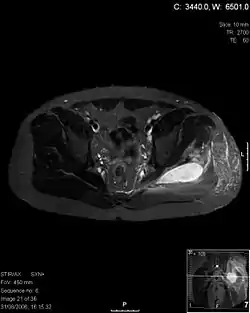

![]() أشعة مقطعية محورية على مستوى T1 توضح التهاب العضلات التقيحي الناتج عن الاصابة بالبكتيريا المكورة العنقودية الذهبية التي تستجيب للميثيسلين. ]] | |

يعتمد تشخيص التهاب العضلات التقيحي على الفحص الاكلينيكي والتاريخ المرضي للمريض. ويظل التصوير بالرنين المغناطسي هو الفحص الأكثر دقةَ لتحديد الإصابة بهذا المرض.[3]